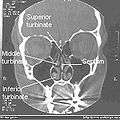

Nasal conchae: Blocked/free

Normal Nose CT Front cross section